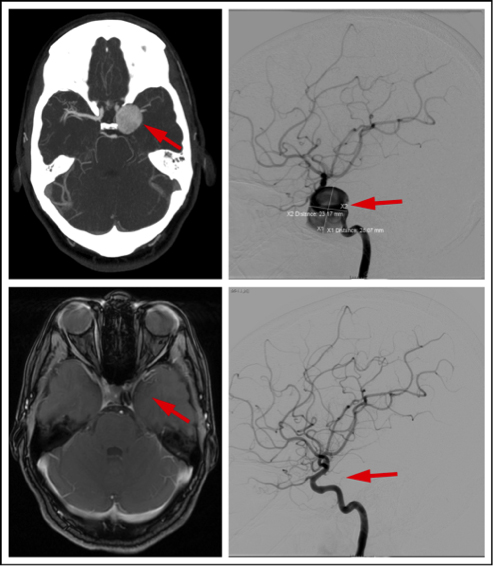

A flow diverter is a stent device that is placed inside a brain artery to treat a cerebral aneurysm. The CT scan points out a giant cerebral aneurysm (arrow, upper left). A cerebral arteriogram provides guidance for minimally invasive treatment of the 28-millimeter aneurysm (arrow, upper right). Treated with a flow-diverting stent, the wall of the artery heals around the flow diverter, and the aneurysm becomes walled off, and then disappears on the MRI scan (arrow, bottom left). A final arteriogram shows complete healing of the artery and no aneurysm (arrow, bottom right).